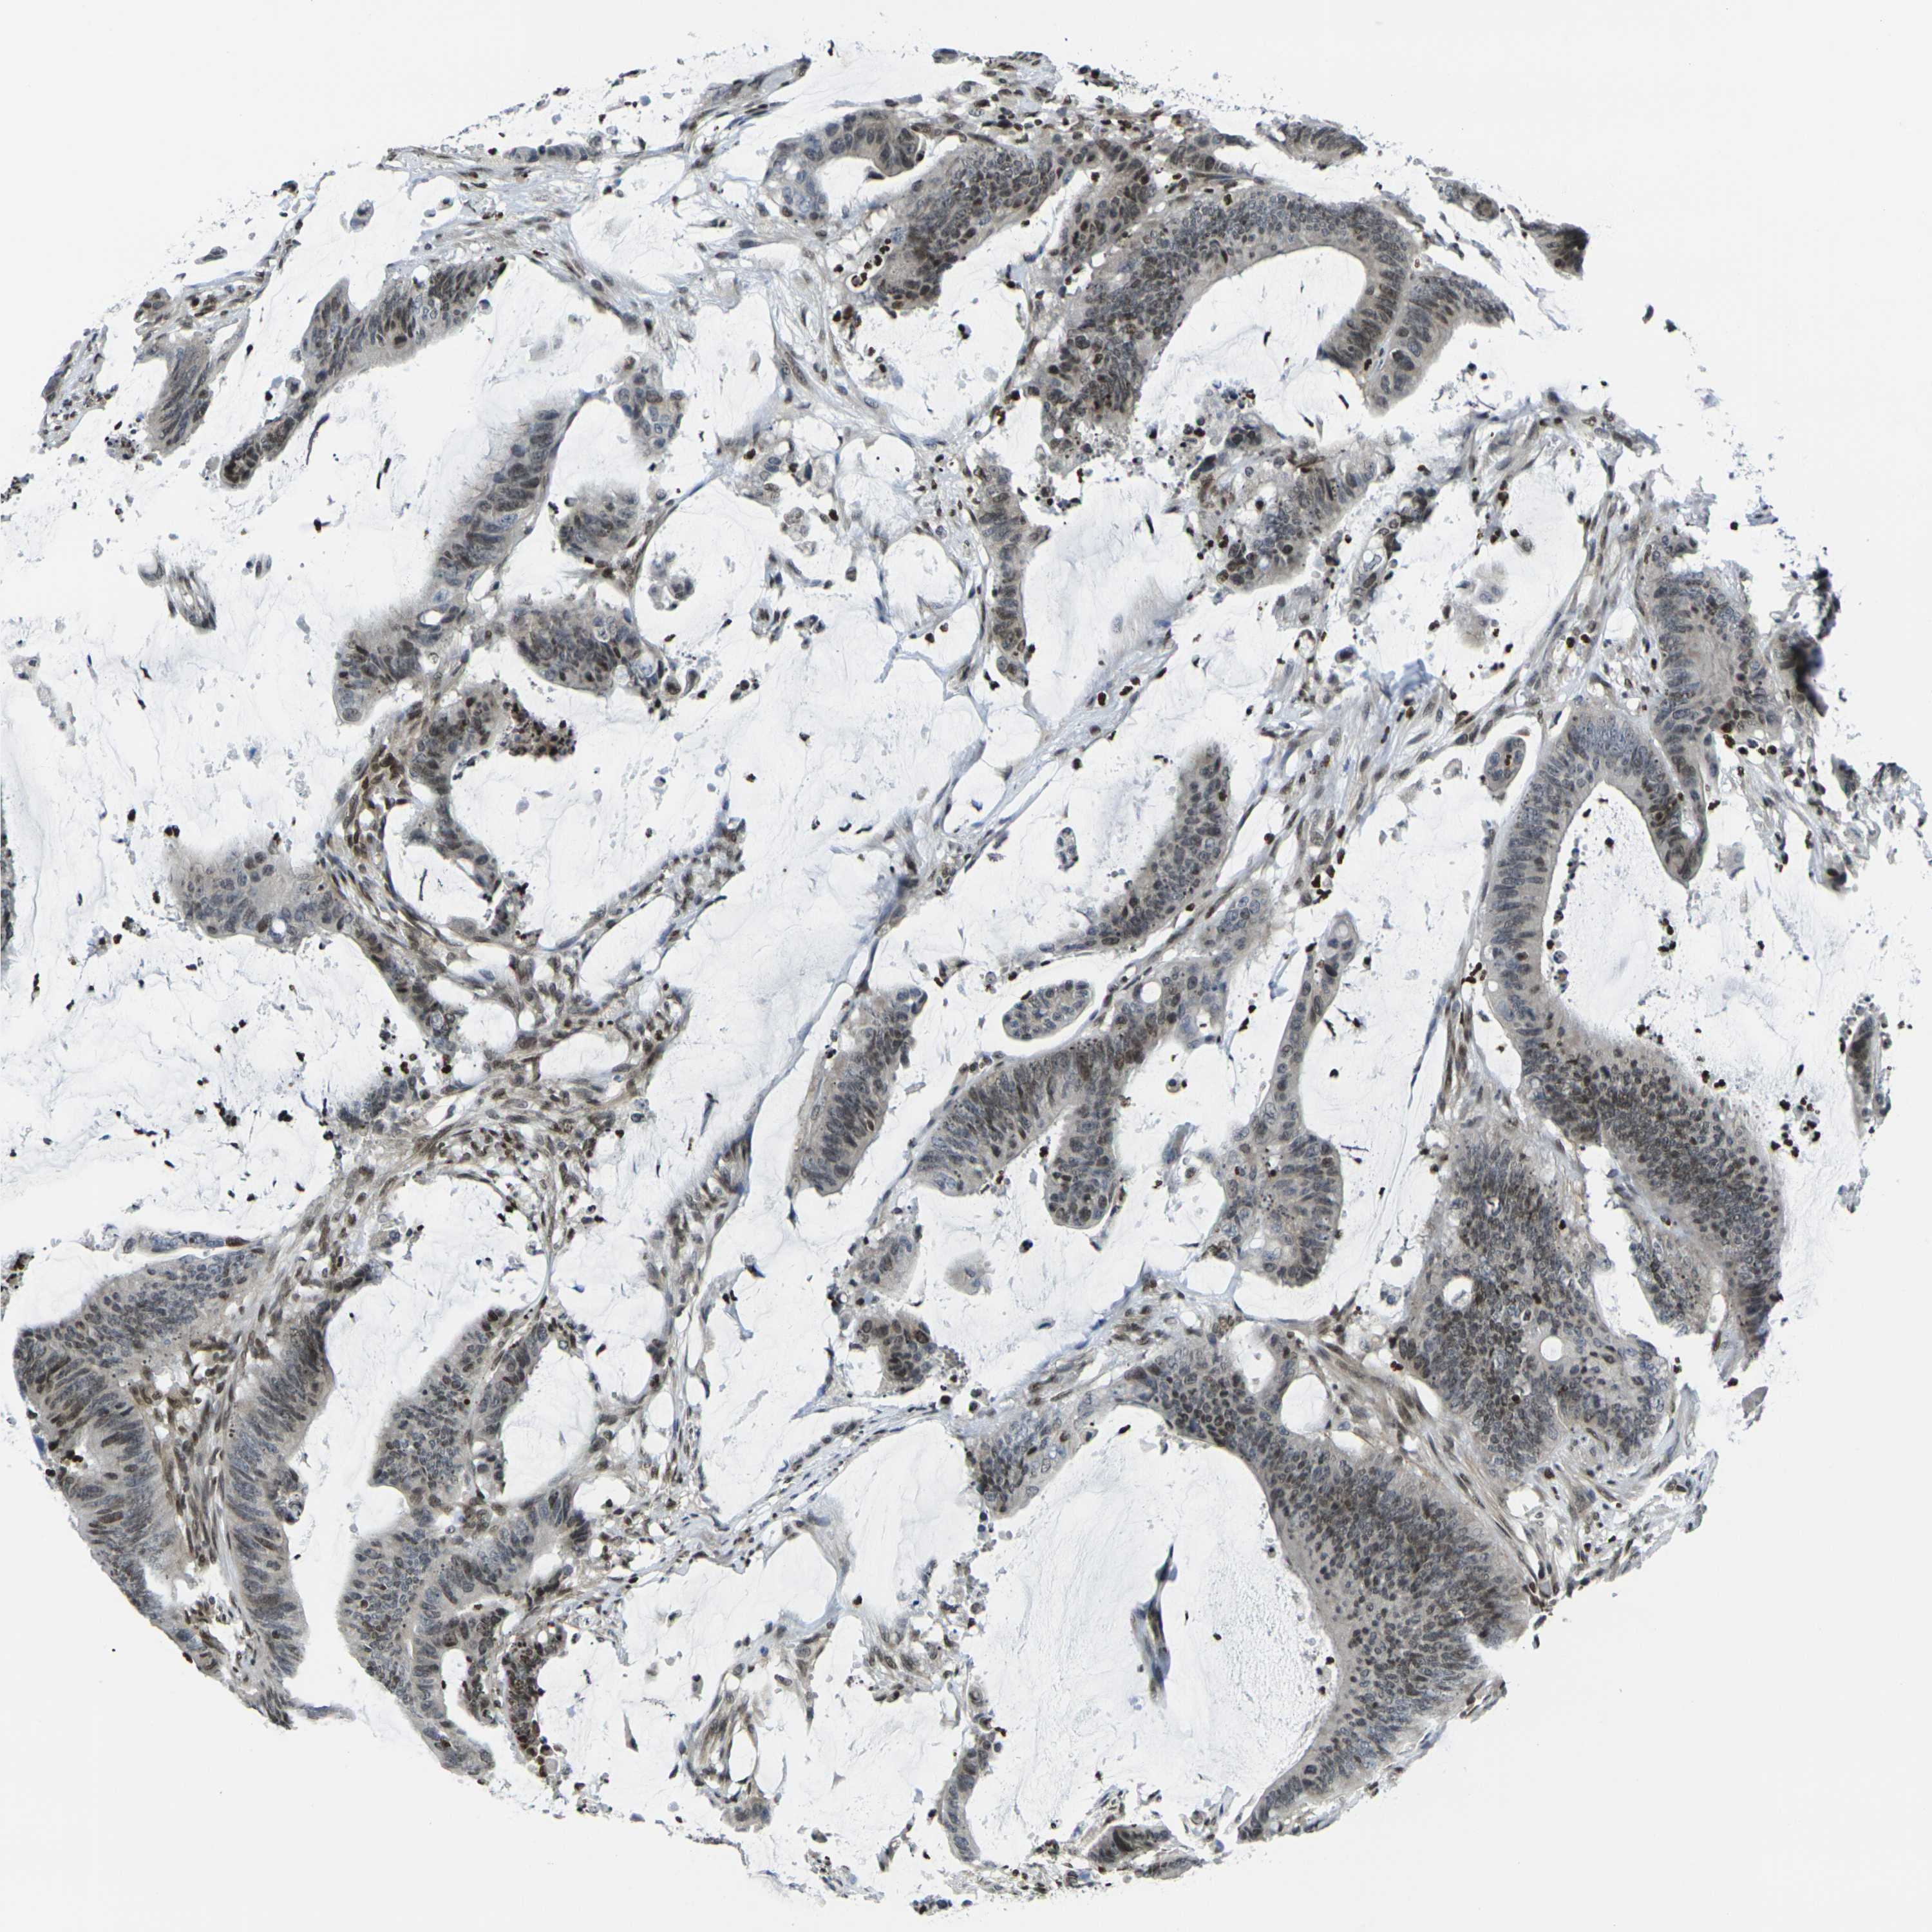

CANCER COLORECTAL CANCER Show tissue menu

Colorectal cancer

Human cancer

Colon adenocarcinoma